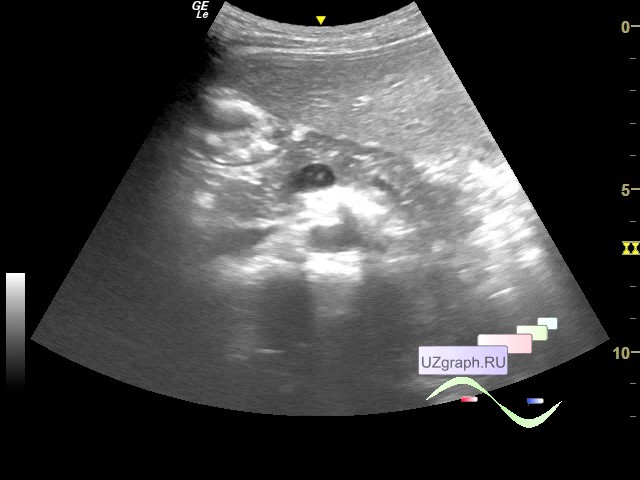

Как выглядит доля Риделя на УЗИ печени